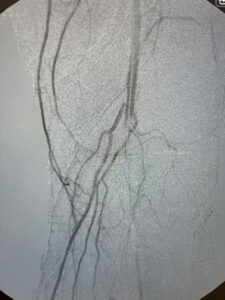

Ενδαγγειακή αποκατάσταση απόφραξης της επιπολής μηριαίας αρτηρίας

ελάχιστα παρεμβατική μέθοδος

24 ωρη παραμονή

Ενδαγγειακή επαναγγείωση της επιπολής μηριαίας αρτηρίας

πλήρη ύφεση της συμπτωματολογίας